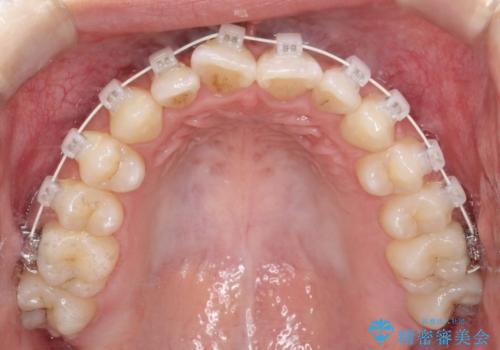

右下第二小臼歯の舌側転移の改善

- 矯正装置

- 審美ワイヤー装置

- 患者様は、右下第二小臼歯が舌側に転移していることが主訴でした。診断の結果、抜歯を伴う矯正治療も検討しましたが、奥歯の遠心移動とIPR(インタープロキシマルリダクション)を行うことで、非抜歯で矯正を進めることが可能であると判断しました。治療計画では、審美ワイヤーを用いた2年間の治療で、歯列を整えつつ、臼歯関係や正中のバランスを維持しながら進めました。

非抜歯矯正では、歯の動きを慎重に調整することが求められます。本症例では、奥歯を遠心に移動させることで、舌側に転移した右下第二小臼歯の位置を改善しました。また、IPRを行うことで歯間スペースを確保し、無理なく歯列の調整を行いました。非抜歯での治療は、特に臼歯関係や正中を保ちながら治療できるというメリットがあり、最終的にはバランスの取れた歯並びを実現できました。審美ワイヤーを使用したことで、治療中も目立ちにくく、患者様の見た目にも配慮した治療を行いました。